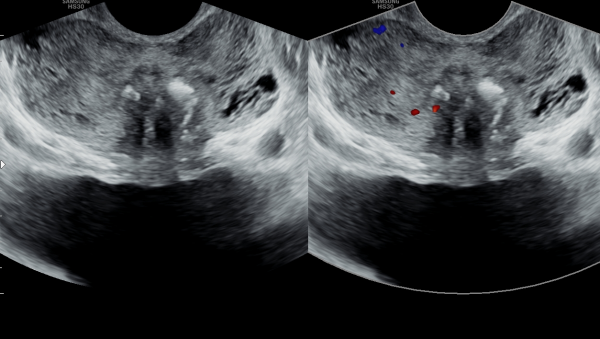

5년뒤 바쁜 일상 생활로 상기 환자분이 적절히 치료를 하지 않고 고환의 통증과 사정 장애와 사정통 그리고 회음부의 통증이 심하다고 내원하여 추적 검사한 경직장 전립선 초음파 검사상 좌우 사정관입구의 결석이 커지고

전립선의 다발성 낭종들이 만들어지고 전립선이 비대해 지고 있는 사진입니다.

Five years later, the patient returned with complaints of worsening testicular pain, ejaculation difficulties, pain during ejaculation, and perineal discomfort, having not received appropriate treatment due to a busy lifestyle. A follow-up transrectal prostate ultrasound showed enlarged stones at the openings of both ejaculatory ducts, multiple new cysts forming in the prostate, and progressive prostate enlargement.